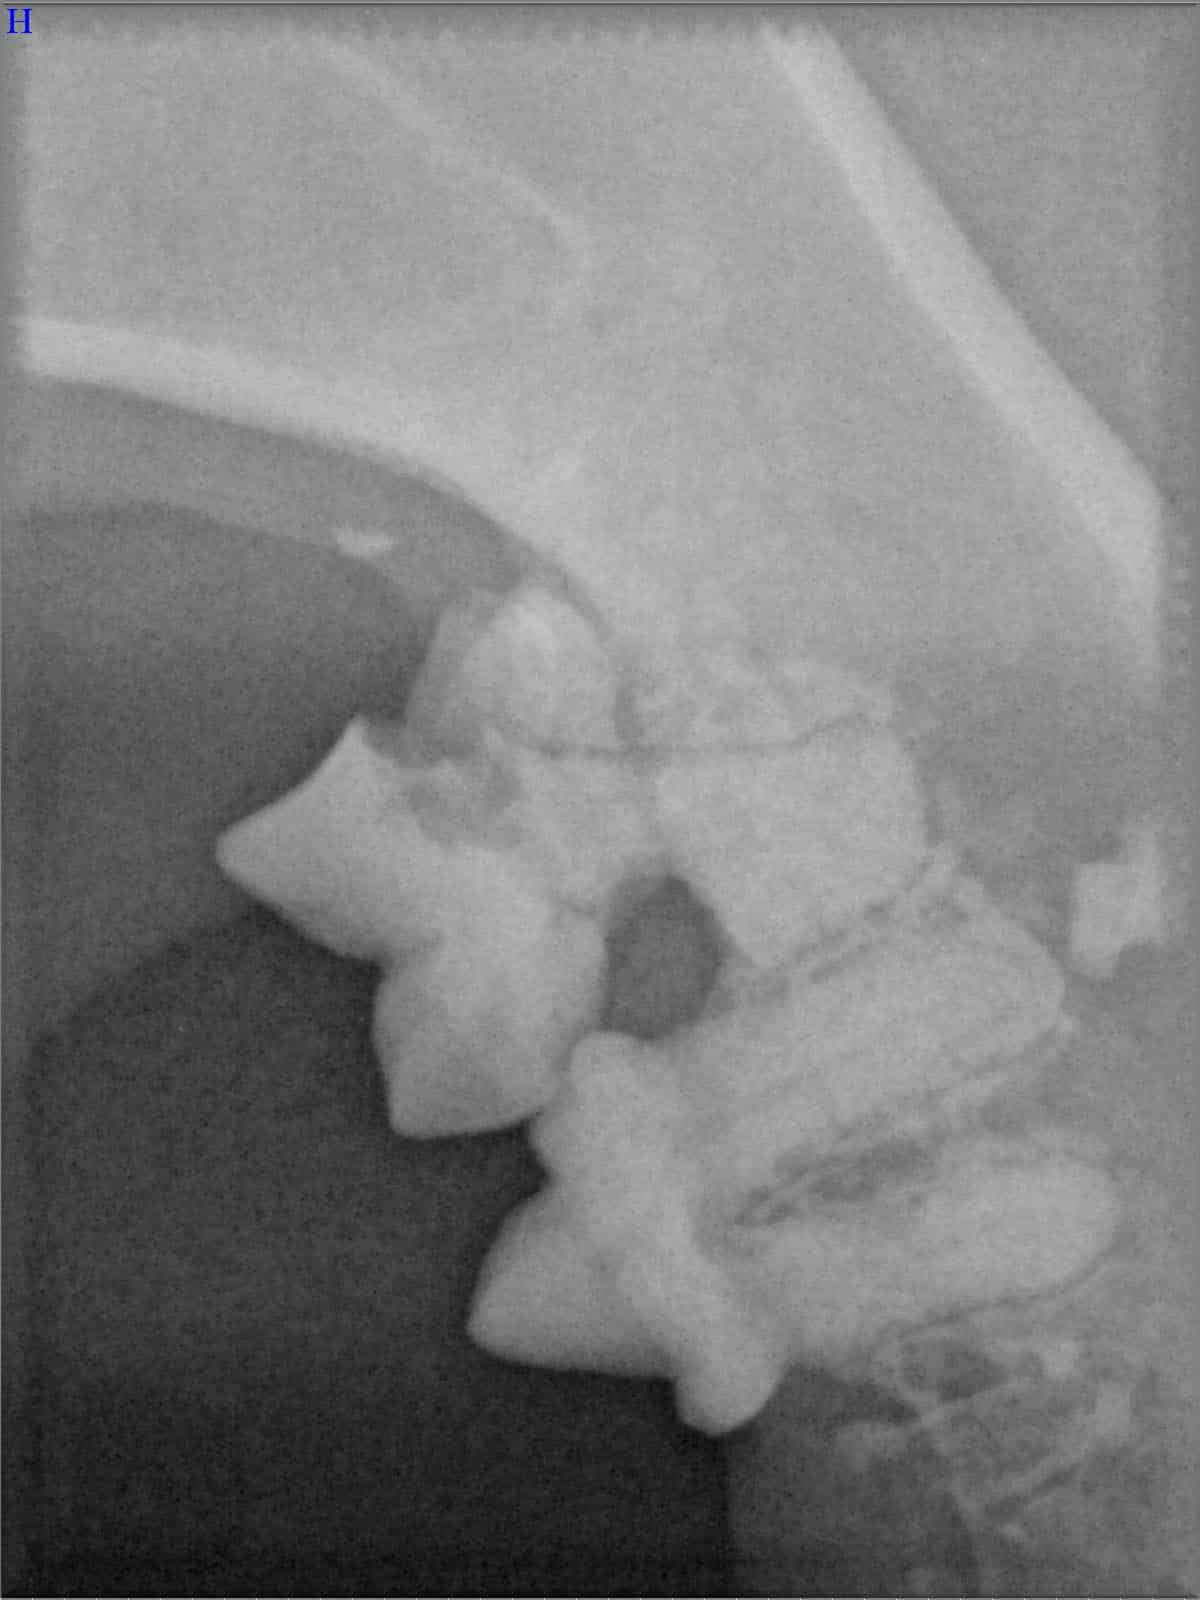

Ein entscheidender Baustein der FORL-Diagnostik ist das dentale Röntgen. Viele Läsionen sind von außen nicht sichtbar und lassen sich ausschließlich mithilfe moderner Röntgentechnik erkennen. In der Hamburger Praxis kommt digitales Dentalröntgen zum Einsatz, das detailreiche Aufnahmen bei geringer Strahlenbelastung ermöglicht. So kann FORL bereits in frühen Stadien diagnostiziert werden.

Das sehen Sie von außen – so sieht es auf den Röntgenbildern aus.

FORL Katze Röntgenbild

Röntgenbilder